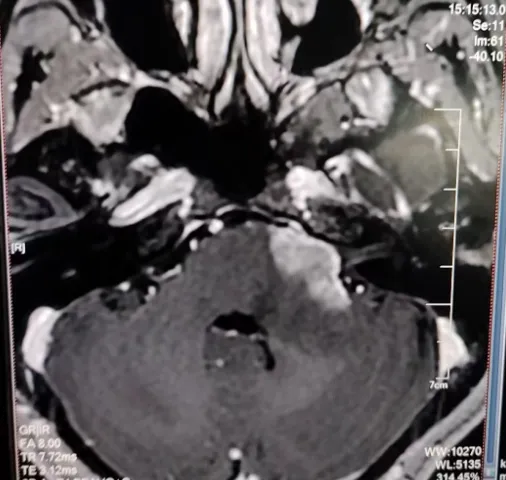

“身边的人现在都说,看起来就像没做过手术一样。”随访时,林女士的这句话也印证了她术后的良好状态。她没有出现面瘫,也没有吞咽问题,术前左脸严重的抽动症状也消失了。巴教授在查看了她的最新核磁共振影像后表示:血管和神经都得到了很好的保护,也没有肿瘤残留。

虽然多数磁共振成像可以判断出占位类型,但诊断不明的情况确实也不少见。文佳为了彻底搞清楚自己的病情,她进行了磁共振波谱成像检查,但仍然无法确诊:肿瘤性病变、淋巴瘤、还是脱髓鞘?

1、“延髓左侧、脑桥、小脑中脚存在强化肿瘤,并轻微累及左侧大脑脚。目前具备明确手术指征,需要在肿瘤进一步进展、更多侵犯脑干前尽快手术。”

2、“仅通过磁共振成像无法判断具体的胶质瘤类型,即便加做磁共振波谱成像或其他检查,也无法给出100%精准的结论。无论如何都需要手术,术后可以获得精确的组织病理诊断,并进一步明确病变的基因分型。只有这样,才能决定后续是否需要、以及需要何种辅助治疗。”